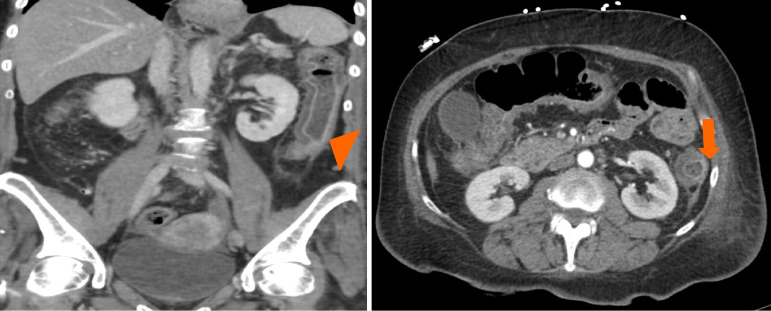

Case summary: A 64-year-old African American woman presented with generalized weakness and non-bloody watery diarrhea of 4-6 weeks duration. She did not have nausea, vomiting or, abdominal pain. She had been on monthly RTX infusions for neuromyelitis optica. She was admitted for septic shock due to pancolitis. Blood investigations suggested pancytopenia and serology detected significantly elevated CMV DNA. Valganciclovir treatment led to disease resolution.